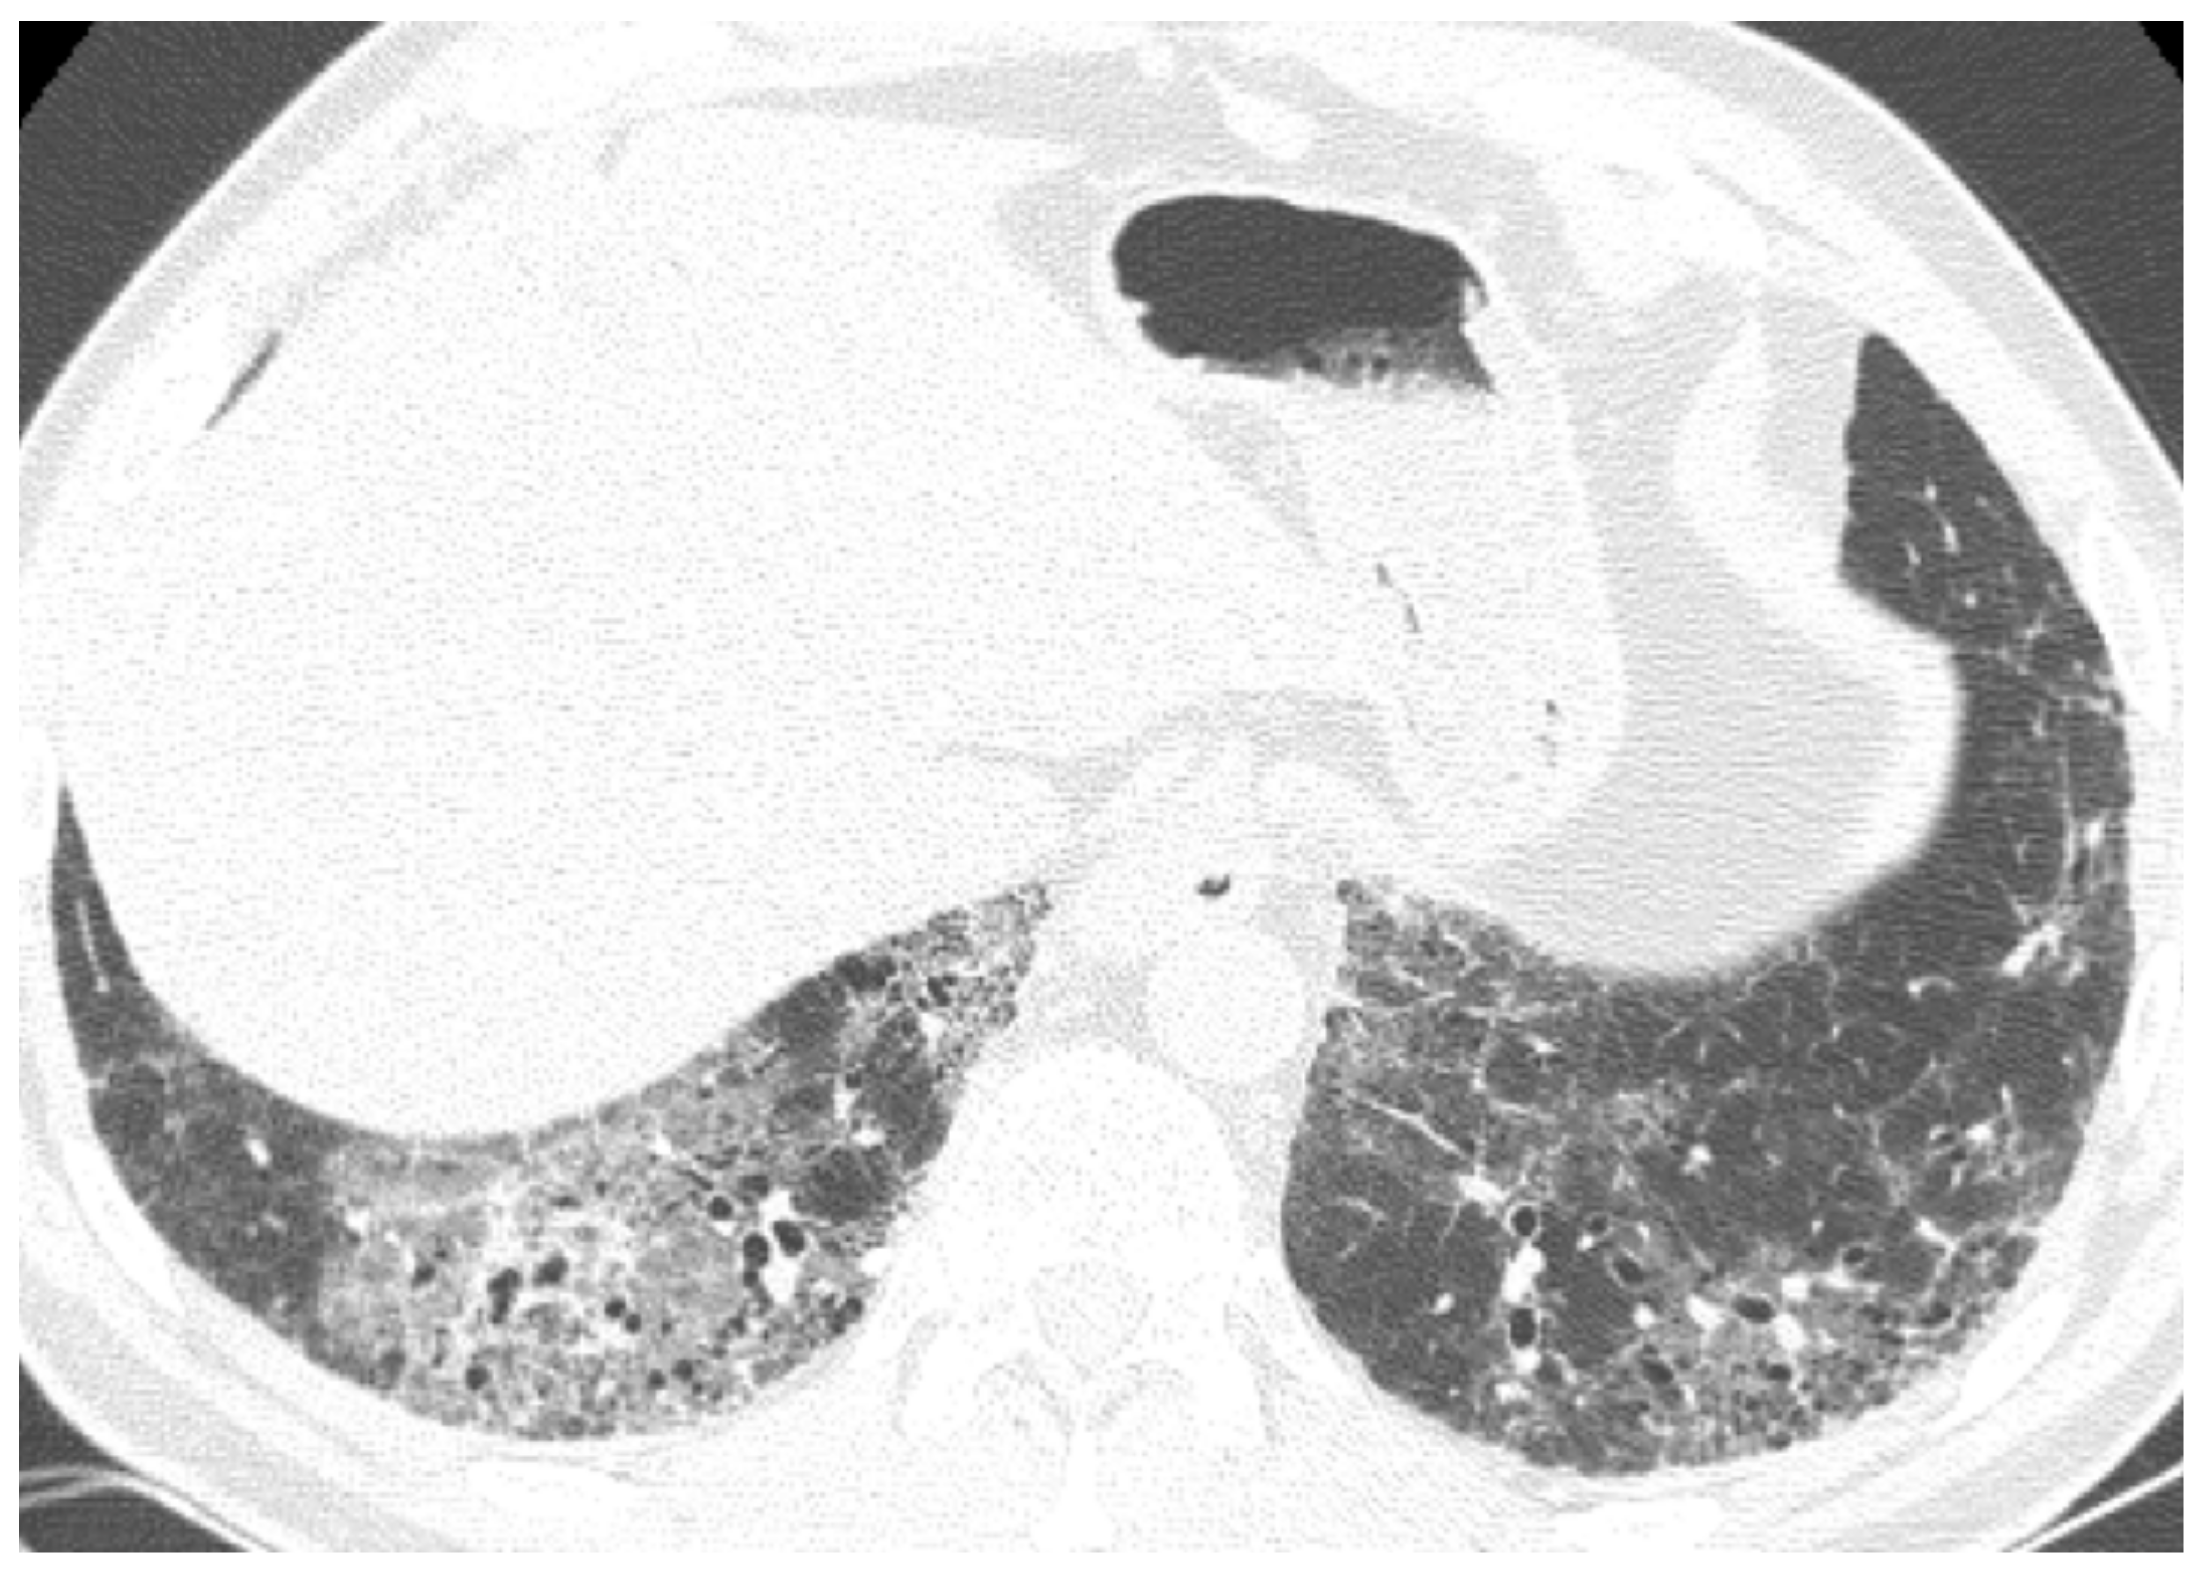

| Chronic | Lung cancer | Ill-defined rounded lesion, mimicking air space consolidation/nodular lesion developing within peripheral and basal honeycombing areas. Ground glass opacity in fibrosis area (mucinous bronchioloalveolar carcinoma). | |

- Lee, H.J.; Im, J.-G.; Ahn, J.M.; Yeon, K.M. Lung Cancer in Patients with Idiopathic Pulmonary Fibrosis: CT Findings. J. Comput. Assist. Tomogr. 1996, 20, 979–982. [Google Scholar] [CrossRef] [PubMed]

- Sakai, S.; Ono, M.; Nishio, T.; Kawarada, Y.; Nagashima, A.; Toyoshima, S. Lung Cancer Associated with Diffuse Pulmonary Fibrosis: CT-Pathologic Correlation. J. Thorac. Imagin. 2003. [Google Scholar] [CrossRef]

- Jang, H.J.; Lee, K.S.; Kwon, O.J.; Rhee, C.H.; Shim, Y.M.; Han, J. Bronchioloalveolar carcinoma: Focal area of ground-glass attenuation at thin-section CT as an early sign. Radiology 1996. [Google Scholar] [CrossRef] [PubMed]

- Oh, S.Y.; Kim, M.Y.; Kim, J.E.; Kim, S.S.; Park, T.S.; Kim, D.S.; Choi, C.M. Evolving early lung cancers detected during follow-up of idiopathic interstitial pneumonia: Serial CT features. Am. J. Roentgenol. 2015. [Google Scholar] [CrossRef] [PubMed]